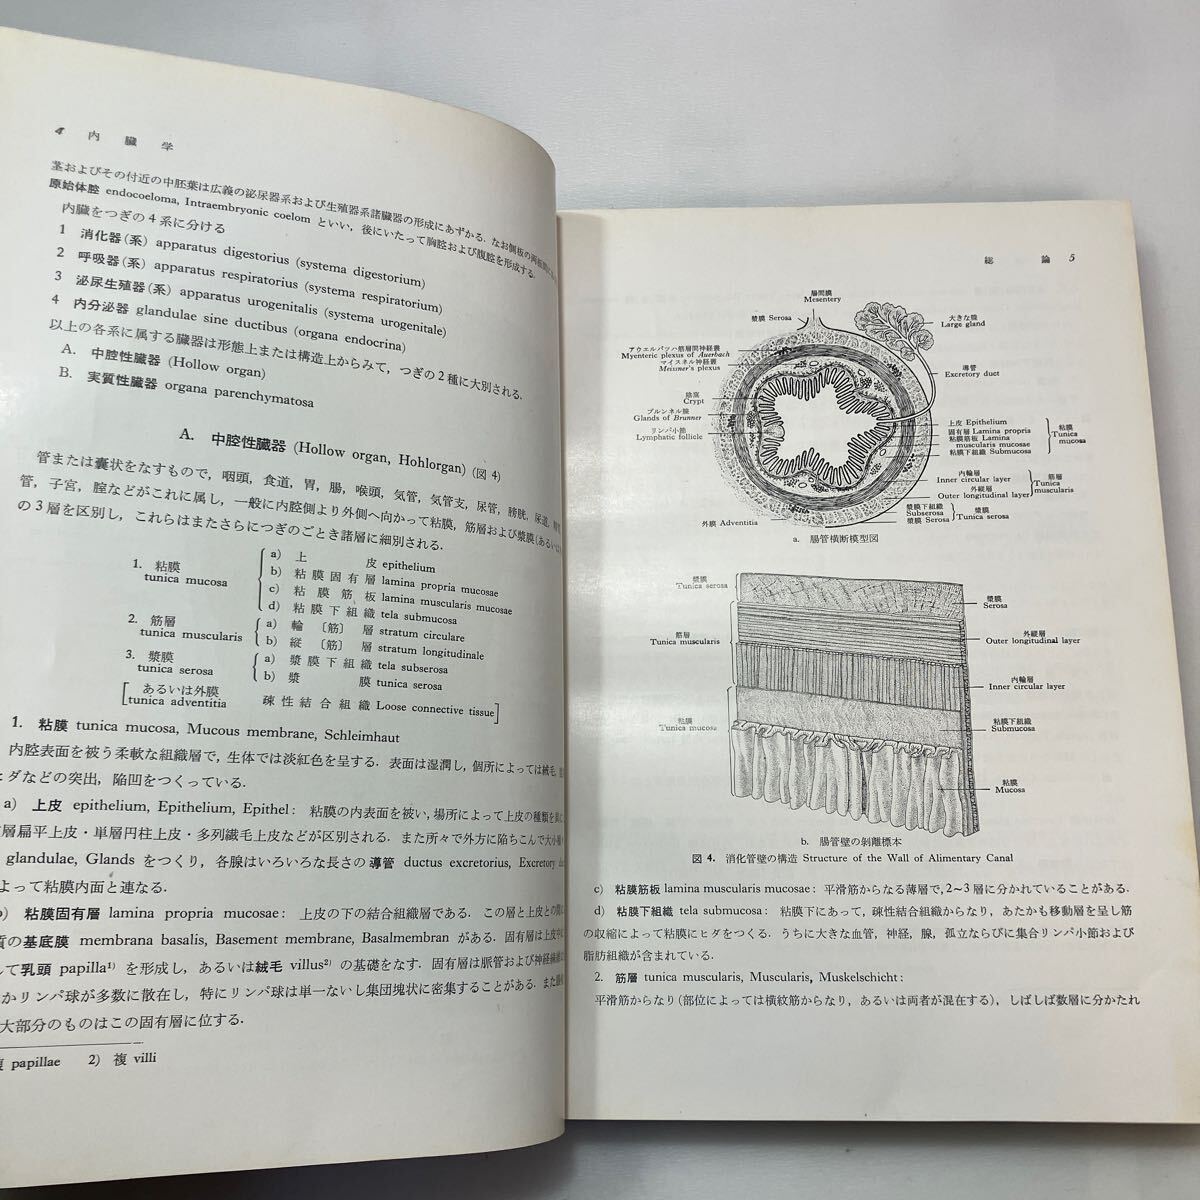

朝倉書店『内科学』(第12版)デジタル付録, zaa-598 日本人体解剖学 第2巻 内蔵学・感覚器学 改訂11版 金子,

zaa-598 日本人体解剖学 第2巻 内蔵学・感覚器学 改訂11版 金子, Amazon.co.jp: v∞ 明治期 皇国千字文解 上下巻 全2冊揃い 藤川,

f23122316〇明治11年 太陽暦 頒暦証付き〇和本古書古文書 / ひ, zaa-598 日本人体解剖学 第2巻 内蔵学・感覚器学 改訂11版 金子,

zaa-598 日本人体解剖学 第2巻 内蔵学・感覚器学 改訂11版 金子, 牛痘発蒙や虎狼痢治準ほか江戸期医学の和本(古典籍)を出張買取